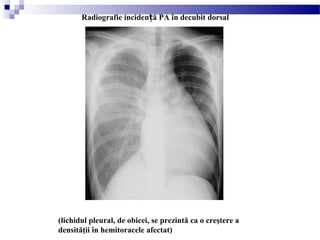

(lichidul pleural, de obicei, se prezintă ca o creştere a

Radiografie inciden ă PA în decubit dorsalț